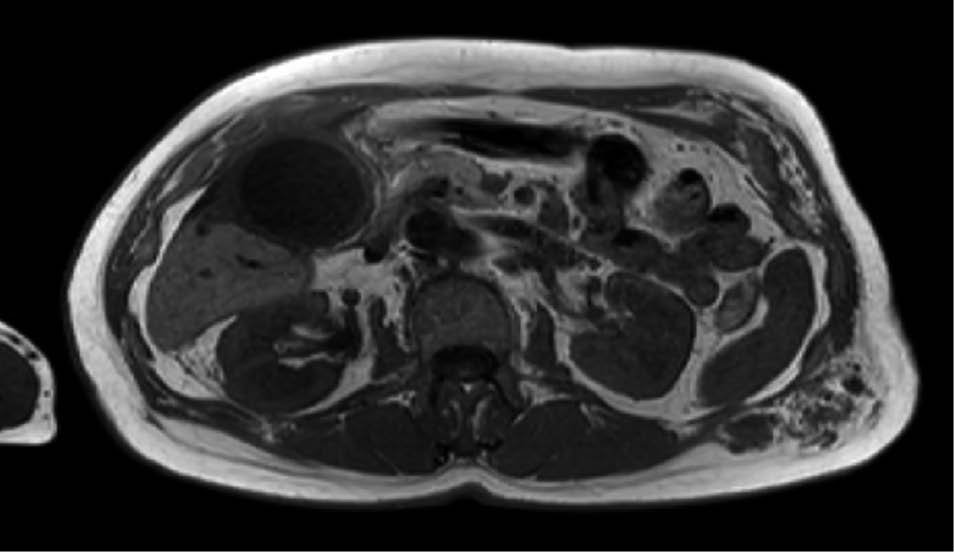

Aufgrund der symptomatischen Cholezystolithiasis nach stattgehabter akuter Cholezystitis wurde die Indikation zur elektiven laparoskopischen Cholezystektomie gestellt. An diagnostischen Verfahren wurden auswärts ein Angio-MRT (Abb. 1 – 4) des Oberbauches und eine Magnetresonanz-Cholangiopankreatikographie (MRCP) durchgeführt, welche eine Cholezystitis bei Cholezystolithiasis und eine beginnende Leberzirrhose nachweisen konnten. Im Rahmen der präoperativen Vorbereitung wurde eine Echokardiographie durchgeführt, in welchem eine Herzinsuffizienz infolge der Volumenbelastung durch die AV-Shunts i.R. des KMS und eine „Cirrhose cardiaque“ ausgeschlossen werden konnten. Als Marker einer intravasalen Gerinnungsaktivierung wurden erhöhte Prothrombinfragmente, D-Dimere und eine erniedrigte Antiplasmin-Konzentration sowie eine gesteigerte Fibrinolysekapazität detektiert. Eine sekundäre Thrombozytopenie oder eine Fibrinogen- und Faktor-XIII-Verminderung konnten ebenso wie das Vorliegen eines erworbenen von-Willebrand-Syndroms ausgeschlossen werden.

In einer hämostaseologischen Vorstellung wurde die Pausierung der Thrombozytenaggregationshemmung über 7 d unter „Bridging“ mittels niedermolekularem Heparin und eine medikamentöse Hemmung der Hyperfibrinolyse durch Tranexamsäure bis zum 3. postoperativen Tag bzw. in Abhängigkeit von Klinik und des hämostaseologischen perioperativen Monitorings empfohlen. Als perioperative Antibiotikaprophylaxe wurde Imipenem eingesetzt. Der Kameratrokar wurde entsprechend der aus dem Angio-MRT bekannten linksseitigen Ausprägung der Gefäßmalformationen (Abb. 1 – 4) in typischer Nabelposition platziert.

Abb. 2: MRT:

A) T1 axial kutan am Arcus

B) T1 axial – Befund am

M. latissimus dorsi

C) T1 axial – Hauptbefund an der hinteren Axillarlinie

D) T2 coronar – M.-latissimus-dorsi-Linie

E) T2 koronar – Hauptbefund an der hinteren Axillarlinie

F) T2 koronar – kutan am Arcus